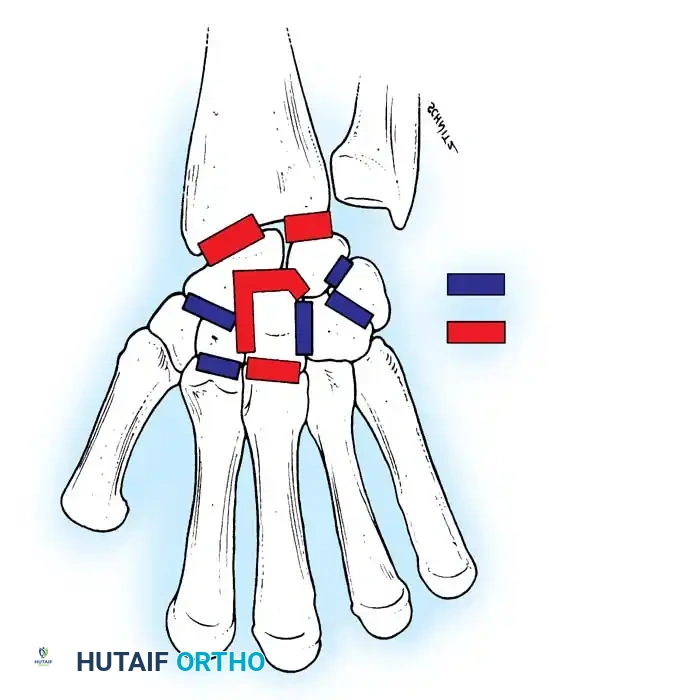

Chronic Instability and TFCC Reconstruction

In chronic settings where the TFCC is irreparable, anatomic ligament reconstruction using a tendon autograft (e.g., palmaris longus) is indicated. The graft is routed through the distal radius and ulnar fovea to recreate the dorsal and volar radioulnar ligaments.

Tendon graft routing through osseous tunnels in the radius and ulna for anatomic reconstruction of the DRUJ ligaments.